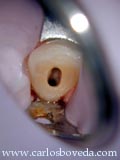

Este caso se refiere a la de una colega Odontólogo, de 34 años de edad, quien muestra la siguiente condición clínica:

cccccc cccccc

( Haga click en las imágenes para agrandar)

Nos refiere que, aún cuando no ha tenido ninguna sintomatología endodóntica, una evaluación clínica y radiográfica general muestra la siguiente situación en el sector antero inferior :

Le preocupa el hallazgo en los caninos inferiores. El canino inferior izquierdo responde las pruebas de sensibilidad dentro de los límites de normalidad, mientras que el canino inferior derecho no responde a estas pruebas. En relación a la estimulación de percusión, ambos dientes responden de manera muy similar a cualquier otro diente sano de su boca.

Su historia clinica general no aporta ningún dato relevante, a excepción de haber sido sometida a una cirugía ortognática de reposición mentoniana y su consiguiente tratamiento de ortodoncia, unos 15 años antes de este momento.